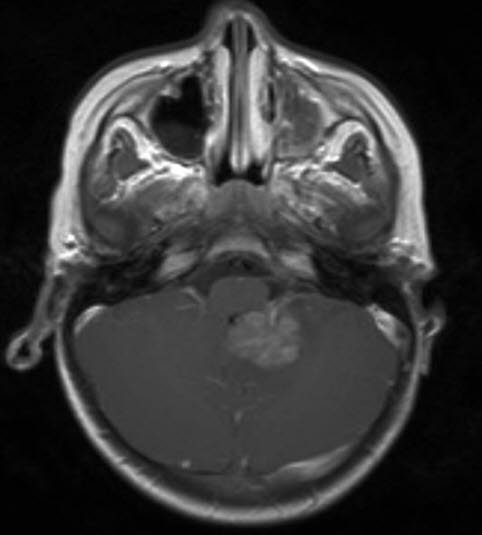

Atypisk teratoid rhabdoid tumor, aksialt snitt

atypisk teratoid rhabdoid tumor 1

Gjengitt med tillatelse av Radiologisk avdeling, Universitetssykehuset Nord-Norge